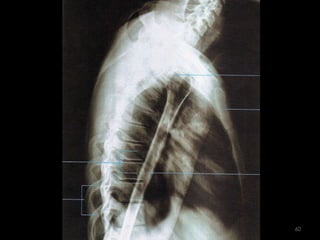

Incidência lateral transtoracica do úmero- método lawrence58

59

60